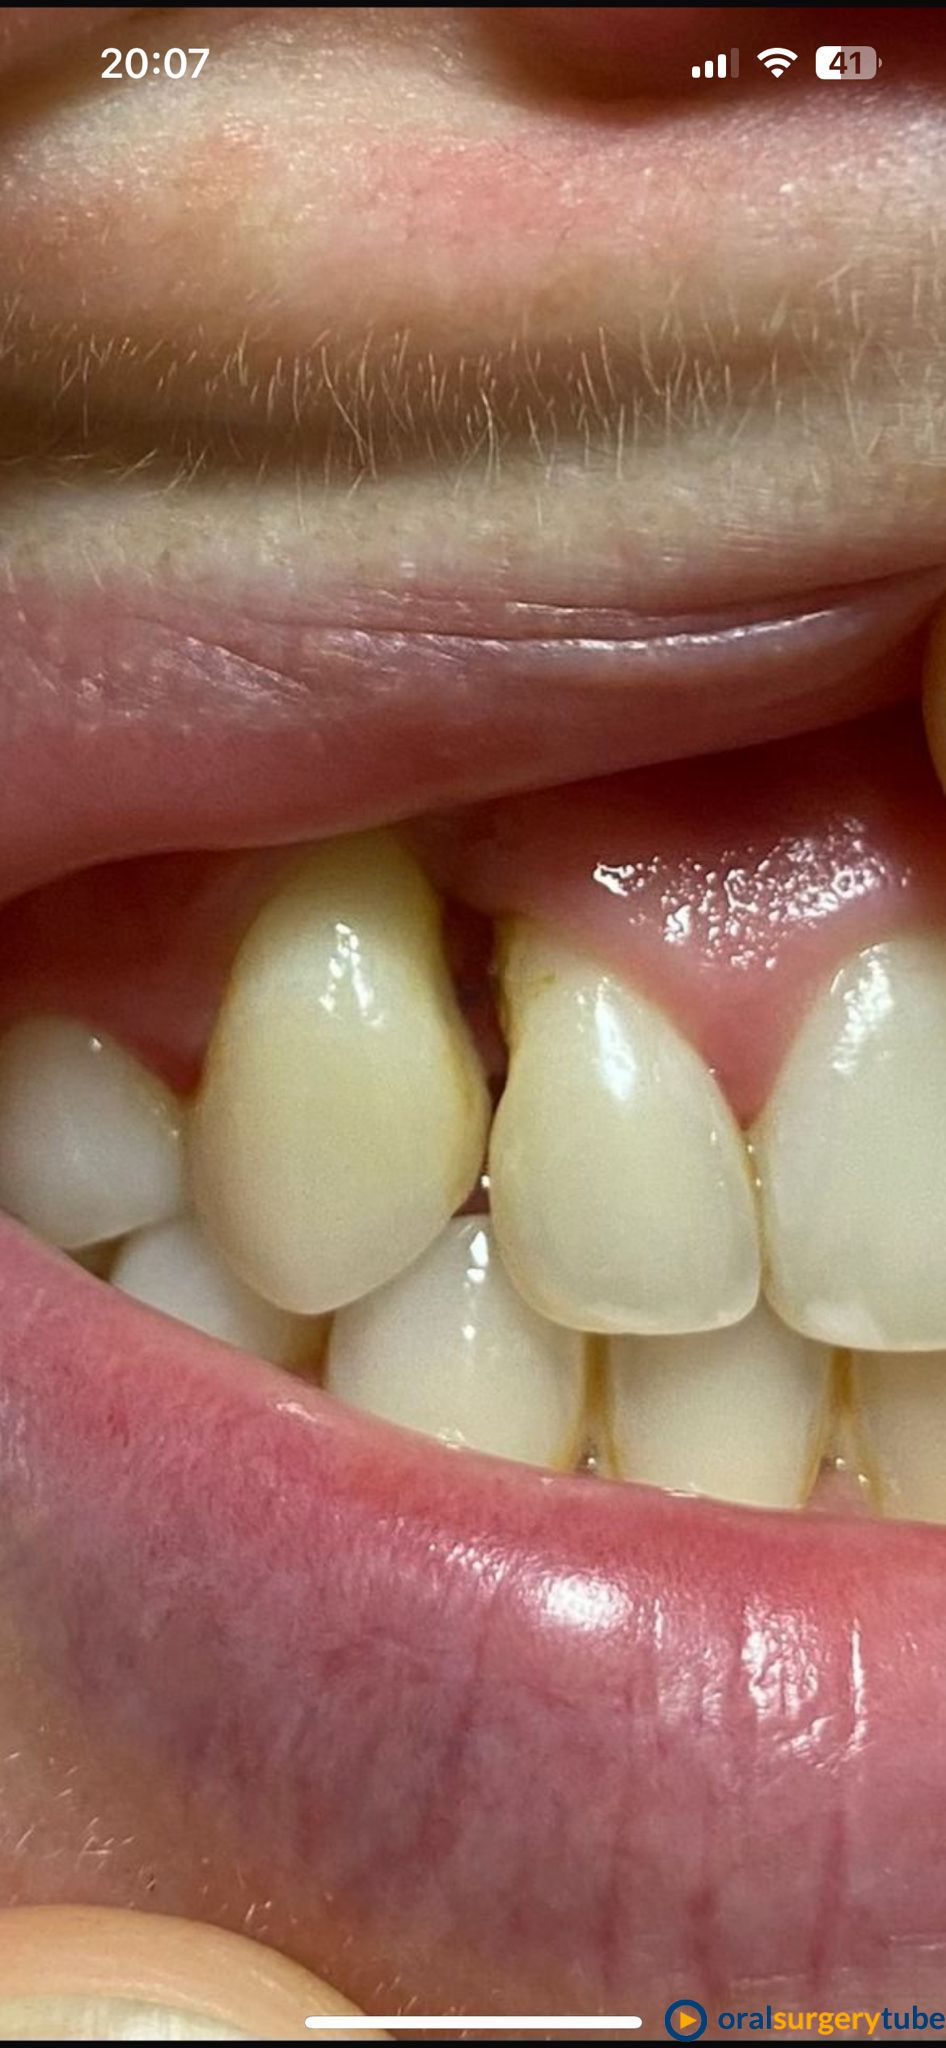

Seguimiento de caso de defecto vertical entre dos dientes (12 y 13) tras cirugía ortognática.

Paciente de mediada edad que es remitida para intentar mejorar el estado periodontal de los dientes 12 y 13 tras cirugía ortognática. A la paciente le habían realizado previamente varios injertos de tejido conectivo y empleo de Emdogain® sin éxito. Se plantea hacer técnica de Wall technique de Zucchelli modificada para simultanear técnicas de regeneración ósea guiada.